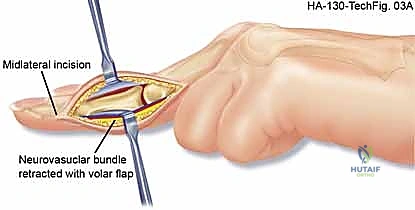

For glomus tumors, we plan a transungual or periungual approach depending on the exact subungual location mapped on MRI. The surgical field must be prepared for potential microsurgical reconstruction. Loupe magnification (minimum 3.5x) is mandatory for all cases, and an operating microscope should be on standby for digital artery repair or nerve neurolysis. The surgical template should utilize extensile incisions (Bruner zig-zag or mid-lateral) to allow broad exposure of the neurovascular bundles proximal and distal to the pathology, ensuring proximal control before entering the tumor bed.

The surgical approach to a vascular tumor is a masterclass in meticulous, bloodless micro-dissection. Once the tourniquet is inflated (using the gravity-elevation technique described above), the skin incision is made. For palmar or digital lesions, Bruner incisions are preferred to prevent flexion contractures. The skin flaps are elevated full-thickness, preserving the subdermal vascular plexus. The fundamental principle of this dissection is to identify normal, healthy anatomy proximal and distal to the lesion before attempting to dissect the tumor itself. The proper digital nerves and arteries must be identified in virgin tissue and traced into the zone of pathology.

When excising a venous malformation or cavernous hemangioma, the lesion will appear as a spongy, purplish mass intimately intertwined with the surrounding fascia, tendon sheaths, or neurovascular bundles. Bipolar electrocautery is the instrument of choice; monopolar cautery risks thermal injury to adjacent nerves. The dissection proceeds circumferentially, utilizing a "peanut" sponge or fine tenotomy scissors to gently sweep normal tissue away from the pseudocapsule of the malformation. Feeding vessels are meticulously skeletonized, ligated with fine silk or metallic clips, and divided. If the malformation infiltrates a digital nerve (a common scenario), an operating microscope is brought into the field, and an epineurotomy is performed to dissect the vascular channels away from the nerve fascicles, accepting a subtotal resection if total excision would result in permanent anesthesia.